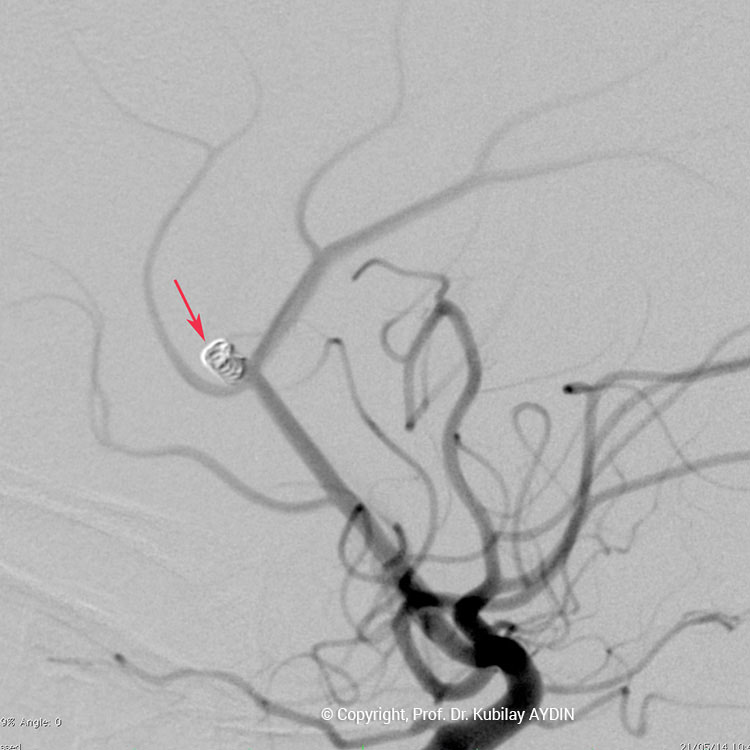

Tüm kapalı anevrizma tedavileri, hasta genel anestezi ile uyutularak gerçekleştirilir. Kapalı anevrizma tedavisinin tüm aşamaları, bacak atardamarı içine yerleştirilen 2 mm çaplı (kurşun kalemden daha ince) bir özel kateter yoluyla uygulanır. Bu küçük giriş noktasından damar içine çok ince (0.5mm çapında) ve yumuşak yapıda mikrokateter adını verdiğimiz özel plastik tüp gönderilir. Anevrizmayı kapatmak için kullandığımız bu mikrokateter, anjiografi cihazında izlenerek anevrizmanın bulunduğu damar içine yönlendirilir. İçi boş, çok ince ve yumuşak bir plastik tüp şeklinde olan mikrokateterin ucu, anevrizma kesesi içine yerleştirilir. Daha sonra bu mikrokateter içerisinden gönderilen platinden yapılmış çok yumuşak “koil” adı verilen tellerle anevrizma kesesi doldurulur. Koiller, anevrizma kesesi içinde bir yumak oluşturup, anevrizma içine kan girişini engeller. Anevrizma kesesi, koillerle tamamen doldurulup, anevrizma içine kan girişi tam olarak durduğu zaman, mikrokateter anevrizma içinden geri alınarak işlem tamamlanır. Anevrizmanın koil adı verilen özel tellerle doldurularak kapatılma işlemine, "koilleme" adı verilir. Anevrizmanın koillenerek kapatılması işlemi, oldukça güvenli ve etkili bir tedavi yöntemidir. Kanamamış beyin anevrizması olan hasta, koilleme yöntemi ile tedavi edildikten 1-2 gün sonra hasta normal günlük yaşamına dönebilir.